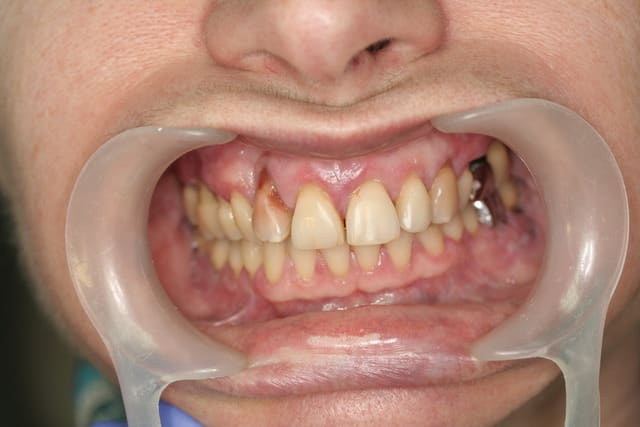

pano initiale et planche 3D montrant qu'en fait les molaires ne tenaient quasi plus que par les racines palatines...